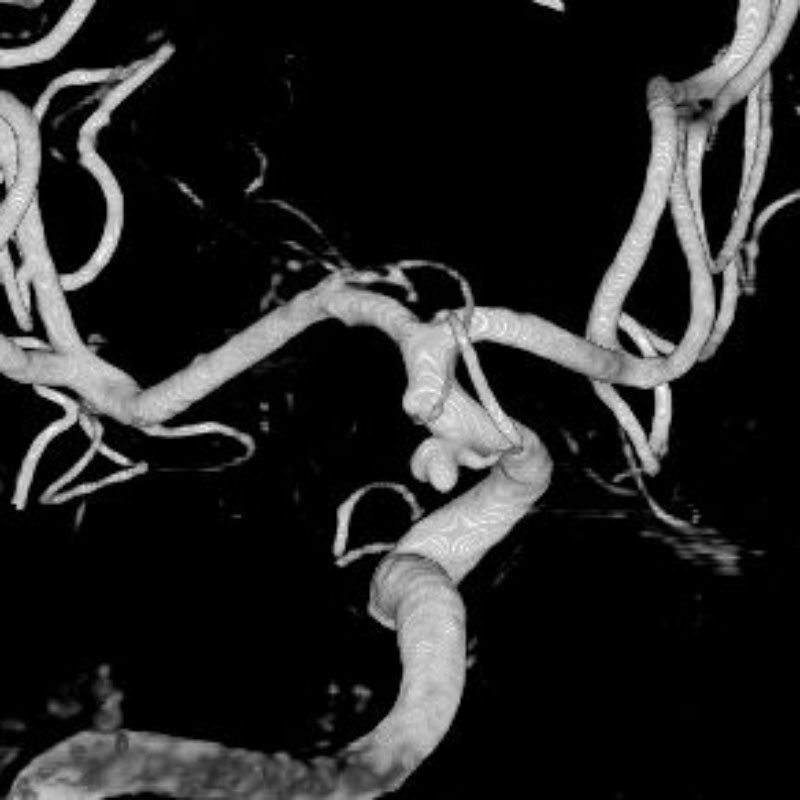

画像